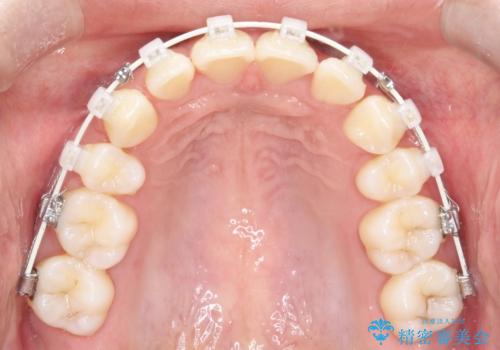

2. 【審美ワイヤー】口元を下げたいの治療中